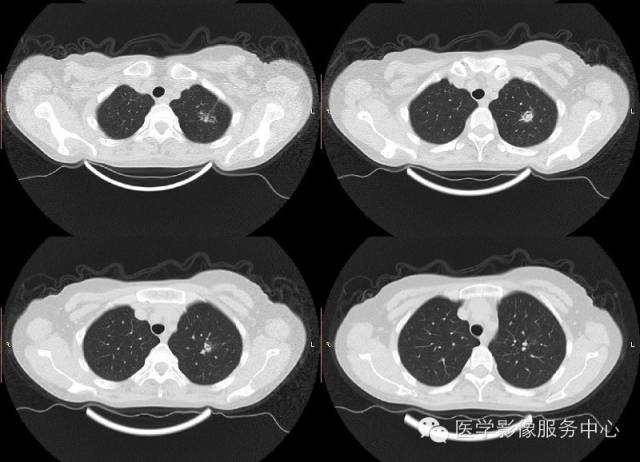

【病例】肺曲菌病1例CT影像表现

女,42岁,间断性咯血一年。

2、单发或多发结节:大多位于肺的中外带,结节大小不一,在CT图像上,其边缘可见略低于结节密度而又高于肺实质的环形“磨玻璃”样改变,称为“晕征”或“环征”。结节 晕征是肺曲菌病较特征的早期表现。CT检查可发现早期肺内较小的结节影。肿块样浸润指病灶直径大于3cm的软组织块影,无分叶及毛刺,周围可出现“晕征”。

3、曲菌球:一般寄生在肺部慢性疾病所致的空洞或空腔内,常见的有结核空洞、支气管扩张、先天性肺囊肿等。空洞大小不等、洞壁薄厚不一,其内曲菌球一般呈圆形或卵圆形,密度均匀,边界光整,在洞内处于游离状态,可随体位改变而移动,曲菌球与洞壁之问形成一新月形的含气腔隙。曲菌球具有特征性的诊断价值。